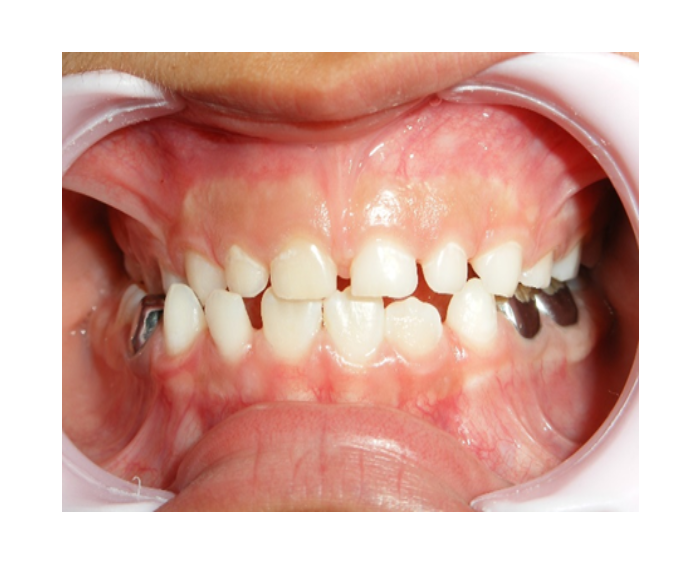

Mordida Cruzada anterior unidental